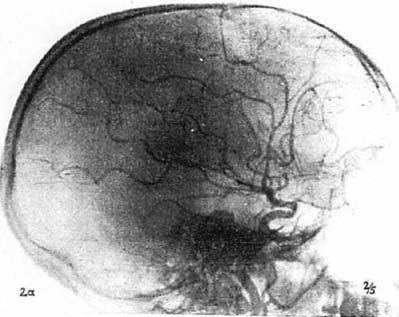

図3. トロトラストによる脳血管造影(前頭葉腫瘍例).それまでのヨード製剤と異なり血管痛がなく,コントラストも良好であった[3]

トロトラストは,ヨードにくらべて造影能がきわめて良好で,ヨードで問題となる静脈内投与における熱感,刺激性がほとんど無いため急速に普及した*.トロトラストの大きな特徴は,血管内投与するとから細網内皮系に取り込まれて肝,脾,リンパ節,骨髄に沈着し,そのままほとんど排出されないことで,生物学的半減期は約400年と推定される.このため,静注24時間以後に腹部X線写真を撮影すると肝,脾が高濃度に描出され,これは 肝脾造影法(hepatolienography)と呼ばれた[2](図2).この他,脳血管造影にも広く使われた[3](図3).投与量は,例えば肝脾造影の場合,25mLを隔日3回[→関連文献],脳血管撮影では1回8~10mLであった[3].